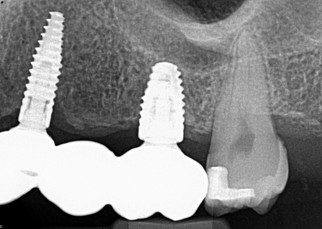

13. (Select ONE or MORE correct answer)

Which of the following is true regarding dental implant at site 2.6?